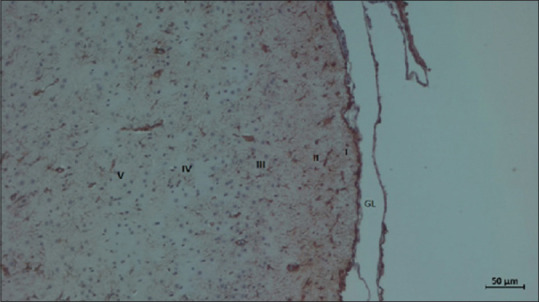

Materials and methods: Adult male Wistar rats, aged 2-3 months, weighing 200-300 g were randomized into four groups of 10 each (control, Group 1, Group 2, and Group 3) to correspond with those used as controls and those that received 500 mg/kg, 1000 mg/kg, and 2000 mg/kg body weight khat extracts, respectively. Fresh khat leaves were purchased from Maua market in Meru, and crude extract was prepared using lyophilization. The control rats were fed on normal diet, while the experimental groups were fed on normal diet and khat extracts using oral gavage for 6 weeks. The animals were sacrificed and their brains were removed. We performed immunohistochemical visualization of astrocytes using glial fibrillary acidic protein. Photomicrographs of the stained sections were transferred to ImageJ Fiji software to study the astrocyte density and astrocytic processes. We used Kruskal-Wallis test to correlate the four animal groups in terms of astrocyte densities.

Results: We observed an increase in the average number of astrocytes with increasing doses of khat compared to controls, with those in Group 3 (2000 mg/kg) having an exuberant reactive astrocytosis. Further, escalating khat doses resulted in increased glial fibrillary acidic protein immunoreactivity in the nuclei and astrocytic processes, gliotic changes, and increased complexity of astrocytic processes.